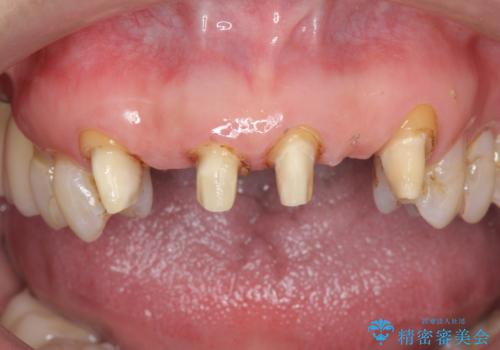

不自然な前歯ブリッジ ジルコニアブリッジによるやり替え

- 20年前に入れたブリッジの見た目の改善を求めて来院されました。

丁寧に現在装着されているブリッジを除去後、精度の高いジルコニアブリッジで審美性の改善を計画します。

- 66万円(仮歯・ジルコニアクラウン×6)費用は治療当時の料金となります